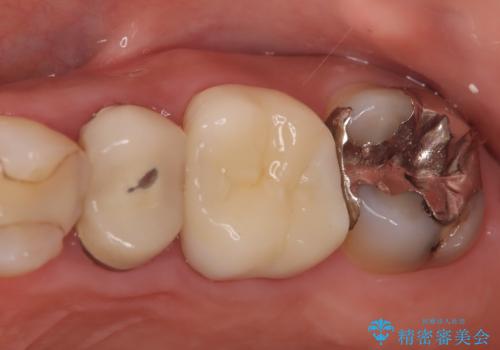

不適な樹脂の詰め物 被せ物で被覆

担当医 岡田康成